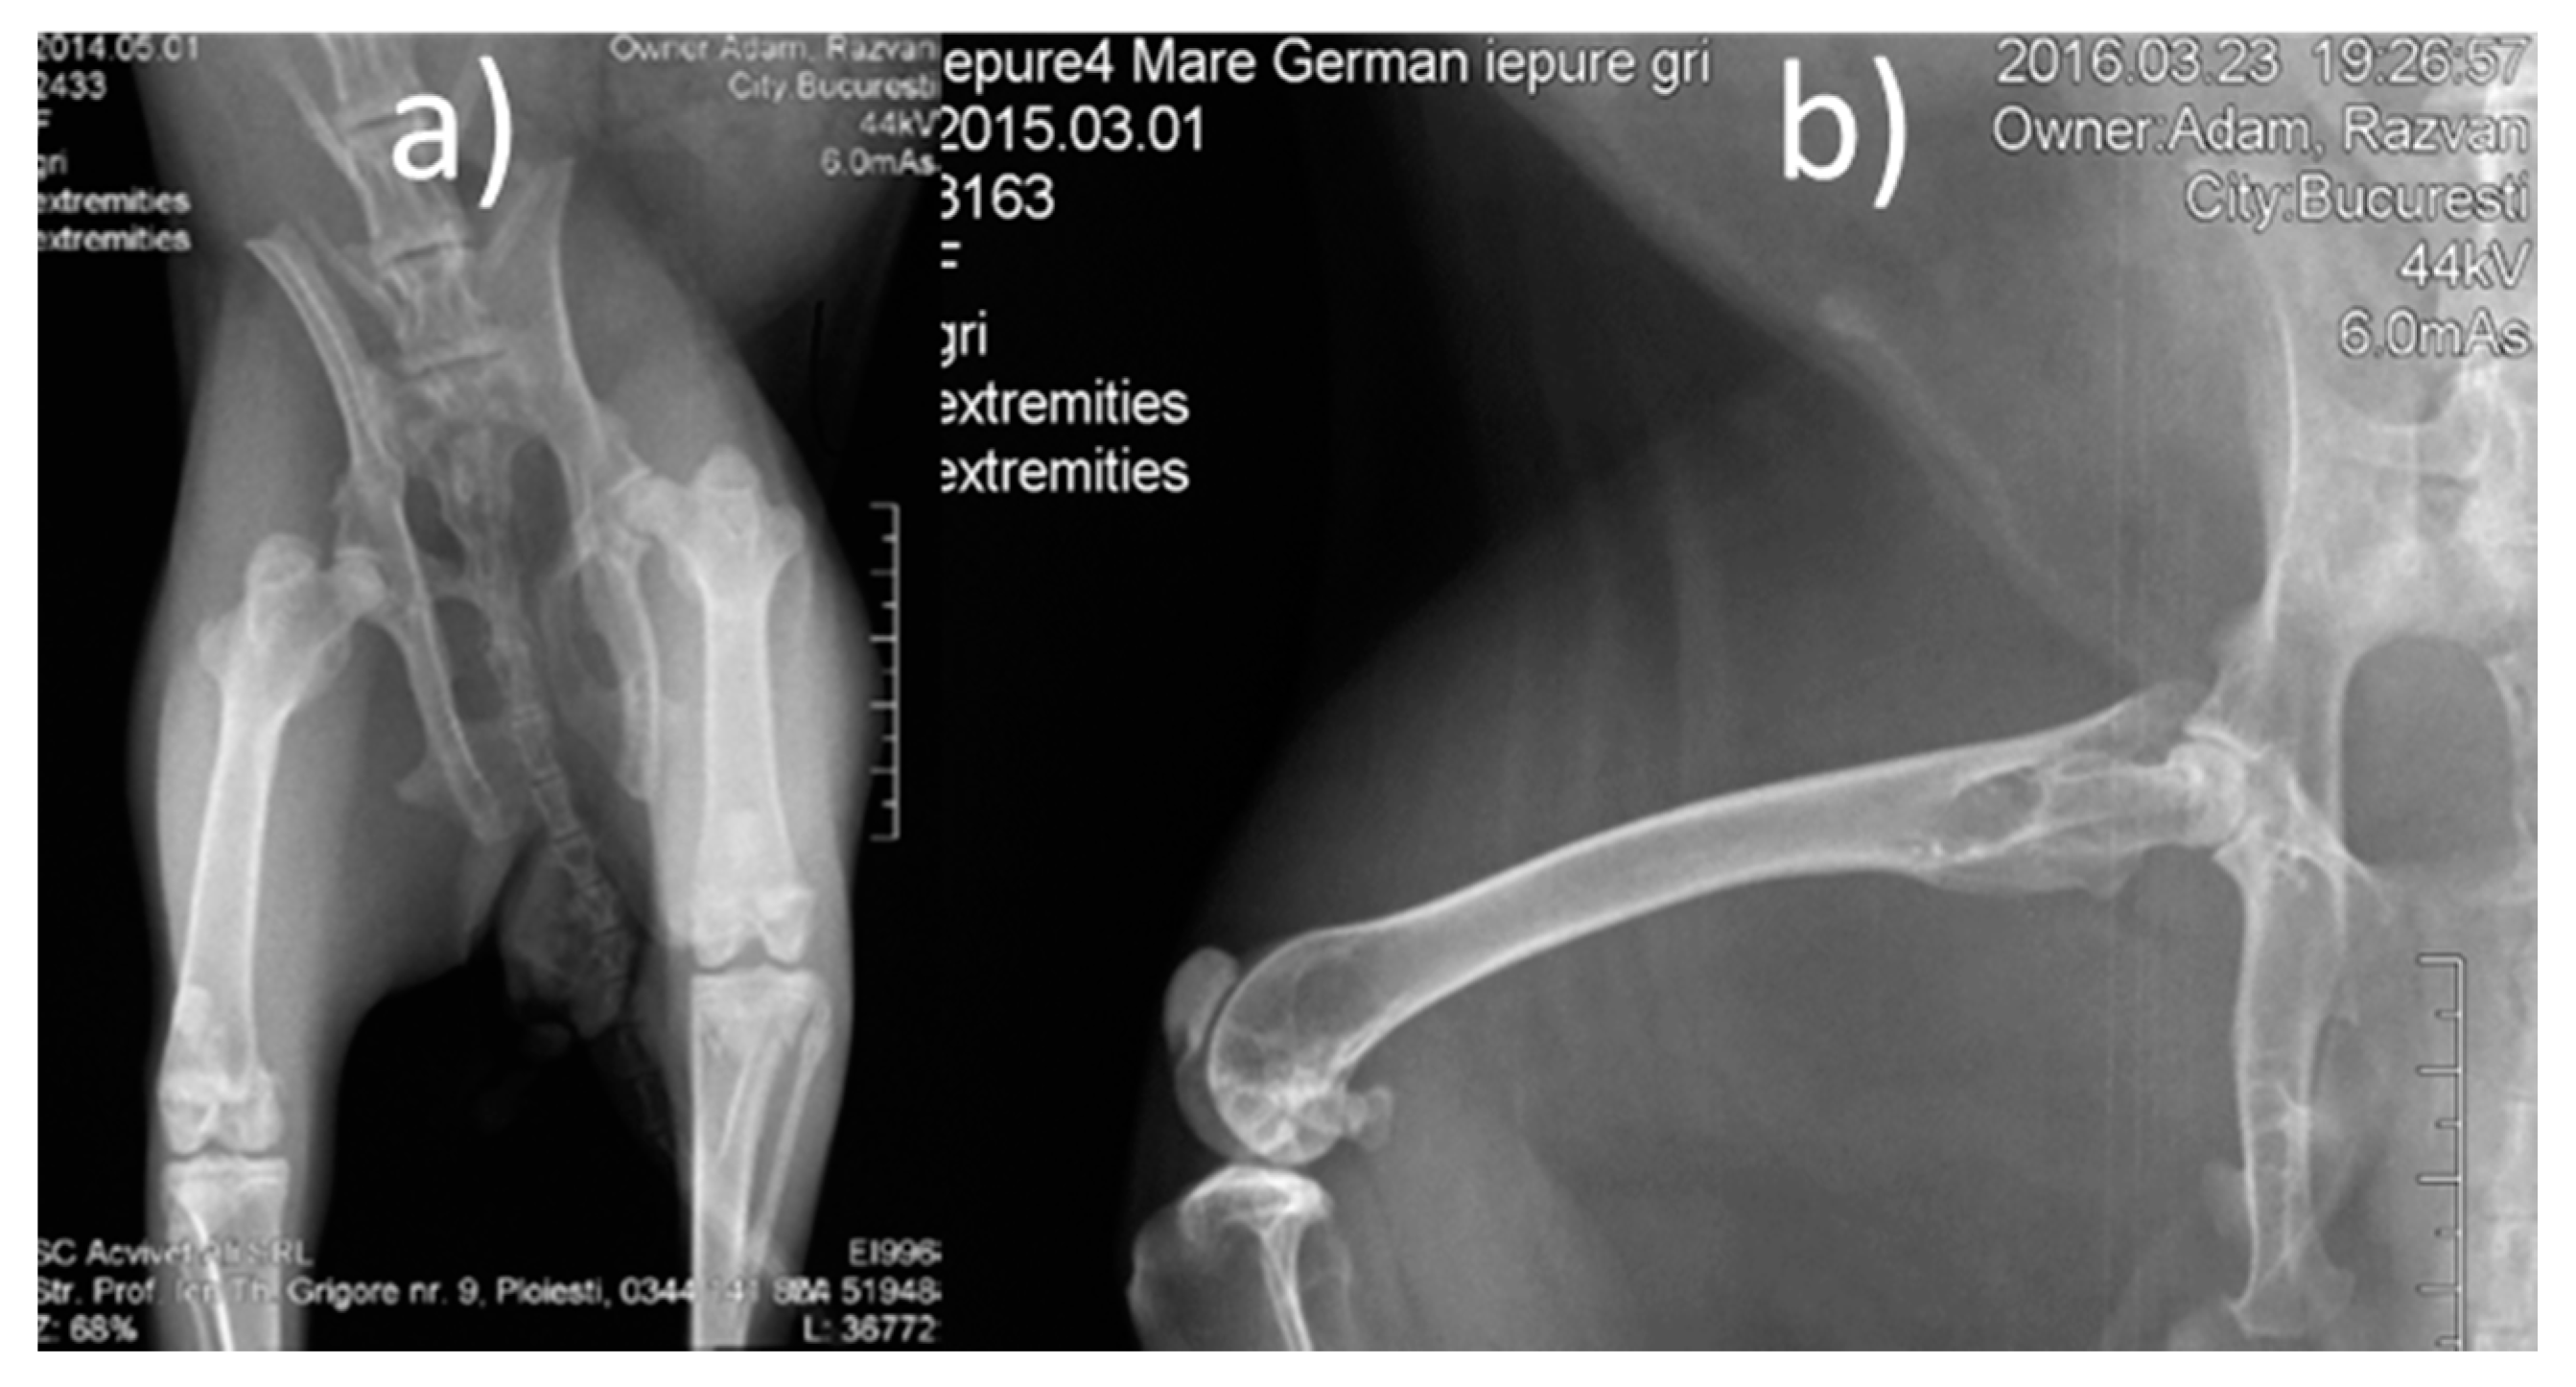

3.2.1. Radiological Follow-Up